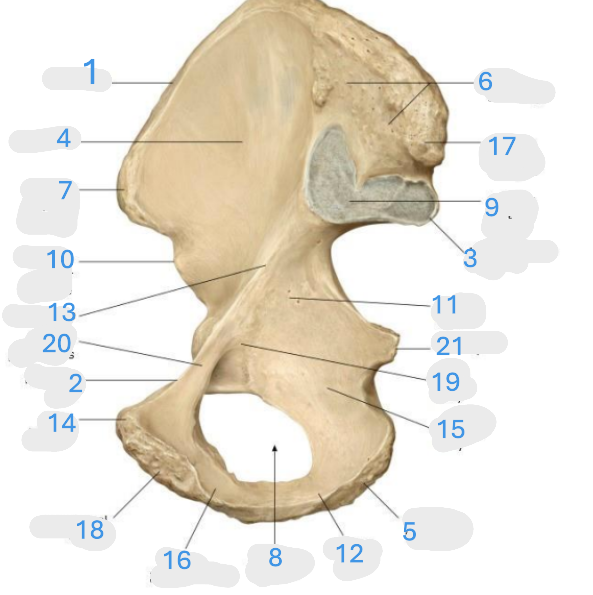

Where is the posterior inferior iliac spine

1

Where is the gluteal surface

2

Where is the iliac crest

3

Where is the posterior superior iliac spine

4

Where is the anterior gluteal line

5

Where is the anterior superior iliac spine

6

Where is the greater sciatic notch

7

Where is the inferior gluteal line

8

Where is the ischial spine

9

Where is the acetabular rim

10

Where is the lesser sciatic notch

11

Where is the obturator foramen

12

Where is the ischial tuberosity

13

Where is the anterior inferior iliac spine

14

Where is the acetabular notch

15

Where is the acetabulum

16

Where is the lunate surface

17

Where is the pubic tubercle

18

Where is the acetabular fossa

19